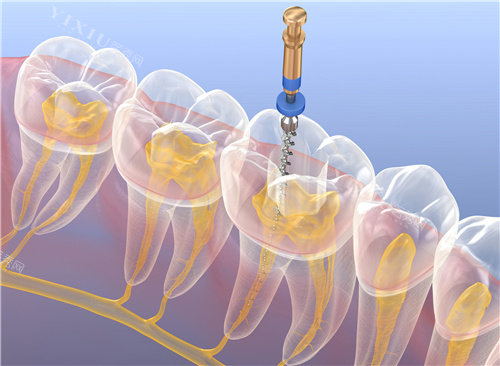

前牙根管治疗:800-1500元

后牙根管治疗:1200-2500元

显微根管治疗:2500-4000元